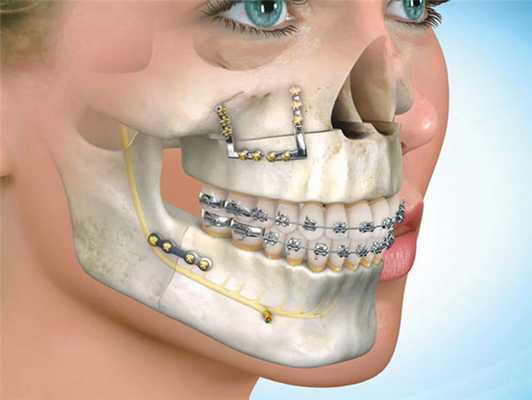

Ортогнатические операции выполняют при остеотомии верхней челюсти, когда проводятся внутриротовые костные разрезы над зубами и ниже обеих глазниц, позволяющие переместить верхнюю челюсть, включая небо и верхний ряд зубов. Такое перемещение позиционируют при помощи заранее изготовленной специальной шины, которая будет надежно гарантировать ее правильное положение нижней челюсти по отношению к мягким тканям.

В процессе проведения манипуляции, хирург делает надрезы костных внутриротовых тканей, расположенных в зоне глазниц и верхней частью зубного ряда.

Такой шаг позволяет доктору беспрепятственно двигать верхнюю челюсть с зубными фрагментами и небным участком. Челюсть устанавливают в заданное положение и крепят посредством специальной каппы.

Верхняя челюсть. Выполняется путем костных внутриротовых тканей. Специалист устанавливает челюсть в заданное положение и крепит посредством специальных конструкций. В завершении производится антисептическая обработка и зашивание десен.